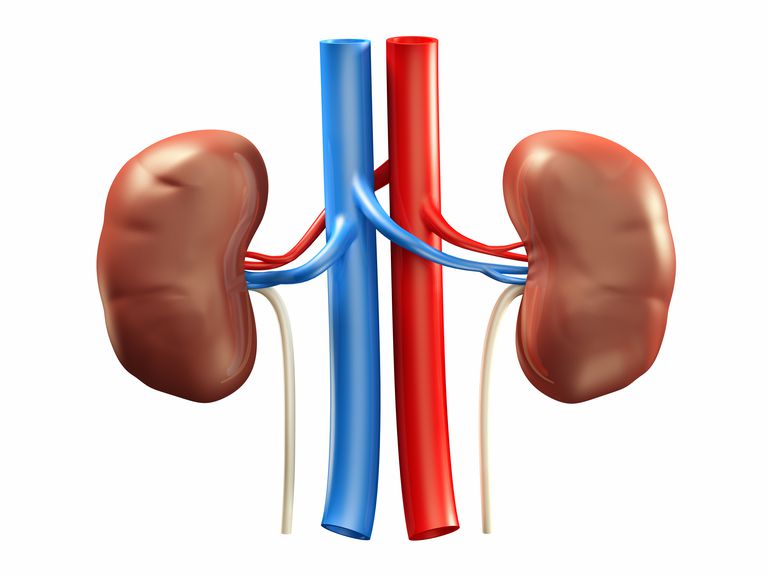

Строение почек человека: Фото и описание